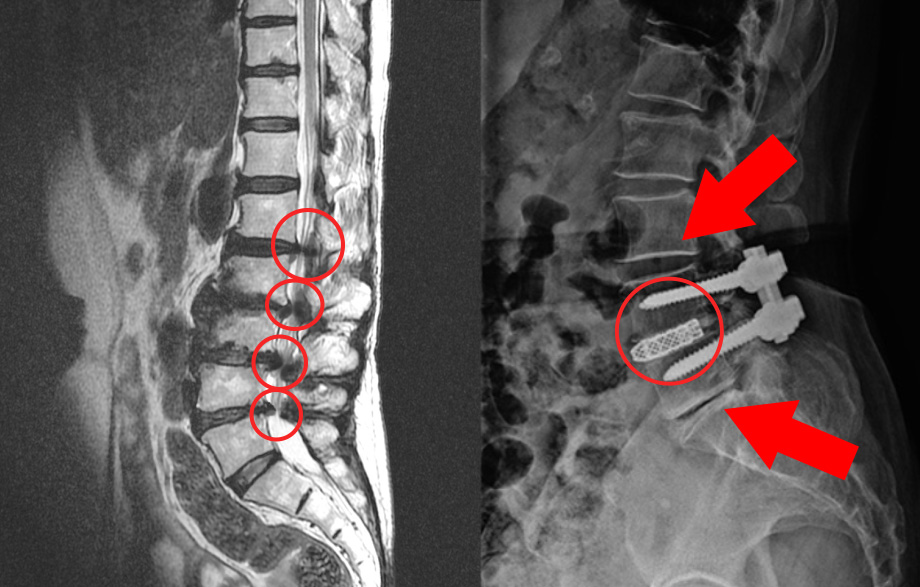

협착증 치료에 대한 잘못된 생각 두 번째, 치료만 하면 끝이라는 생각입니다. 많은 분들이 협착증 치료는 원인을 깨끗하게 해결할 거라고 기대합니다. 그래서 치료만 받으면 다 끝난다고 생각하니까 치료에 대해 조급증을 갖습니다. 그래서 조급하게 치료를 결정하고, 치료를 받고 나면 모든 게 끝날 거라 기대합니다. 이 경우 무엇이 문제가 되느냐? 모든 게 끝났다고 생각하니까 관리를 안 하고, 이게 많은 문제를 일으킬 수 있습니다. 한번 늙어버린 건 다시 젊어지지 않으므로, 치료 후에 어떤 치료를 받고 좋아졌든 지속적인 세심한 관리와 재활운동이 반드시 필요합니다. 치료만 받으면 끝이라고 생각하고 조급함을 가질 경우 생길 수 있는 문제를 먼저 수술 후 발생할 수 있는 문제부터 말씀 드리겠습니다. 협착증 수술은 문제를 일으키는 가장 큰 원인인 퇴행된 척추관 내의 황색인대를 제거하게 되는데, 퇴행이 가장 심한 부분을 수술로 제거하고 나사를 박아 고정시키게 됩니다.

그런데, 보시면 협착증은 이 부분만이 아니라 주변 부분도 다 퇴행되어 있습니다. 그래서 고정술을 한 이후에 이 부분이 구부리지도 펴지도 못하게 되기 때문에 이미 퇴행된 주변 마디에 부담을 주게 됩니다. 주변 마디가 더 많이 구부렸다 폈다가 해줘야 하는 것이죠. 그런데 앞서 말했듯이 협착증 환자는 이미 주변 위아래 마디도 퇴행되어 약해진 상태인데, 추가적으로 부담을 주니까 시간이 흐르면 주변 부위도 문제가 생기게 되는데요. 이것을 인접분절질환이라고 합니다. 일반적으로 척추유합술 후 이러한 문제가 많이 발생하기 때문에 인접분절질환이라는 이름까지 만들어져 있습니다. 이러한 인접분절질환은 특히 수술 후 관리를 잘 못하면 당연히 더 잘 생기기 때문에 유합술을 했다면, 이 인접분절질환이 생기지 않도록 관리를 세심하게 잘 해줘야 합니다.

저희 병원에 오시는 분들의 말씀을 들어보면, 병원에서 인접분절질환에 대해 설명을 안 해준 건지, 아니면 환자분들이 설명을 듣고도 잊어버리신 건지 모르겠지만, 이에 대해 모르는 분들이 아주 많습니다. 그래서 수술 후 관리의 중요성을 잘 인지하지 못합니다. 수술을 하고 나면, 신경을 누르는 부분을 제거했으니까 증상은 물론 좋아지겠죠. 그러나 문제는 증상이 좋아지니까 환자분들이 '이제 농사도 짓고, 등산도 가고 되겠구나' 라는 생각으로 하고 싶은 걸 다 하려고 합니다. 그래서 하고 싶은 걸 다 하면서 무리하다 보면 몇 년 후 다시 주변 부위에서 재발하고, 추가적으로 나사를 박거나 또는 나사를 박자는 말을 듣게 되는 경우가 많습니다. 여러분, 절대로 치료만 받으면 다 끝이라고 생각하고 조급한 마음을 갖지 마시길 바랍니다. 수술을 받든 한방치료를 받든, 협착증은 치료 이후에도 끝까지 갖고 가면서 관리하는 질환입니다. 참고로 저희 모커리한방병원은 인접분절질환으로 인해 재수술을 권유 받으신 분들도 수술 없이 치료하고 있습니다.